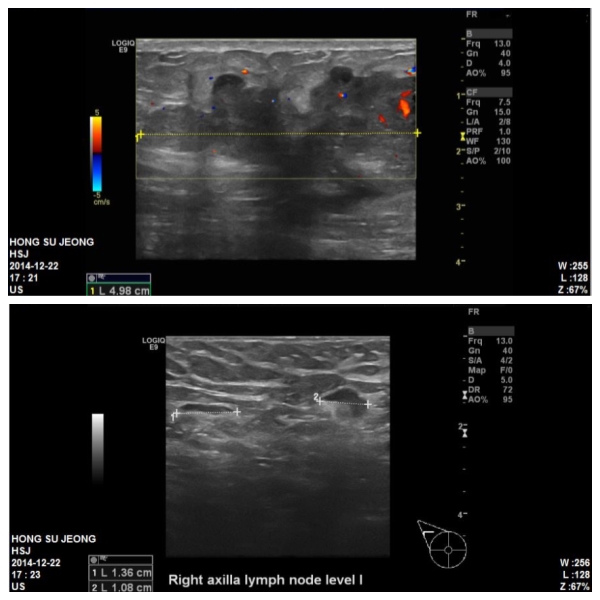

본원 초음파상 우측 5시 방향에 4cm크기의 혹과 겨드랑이 림프절 비대소견있었으며,

그 결과 침윤성 유관암 및

겨드랑이 림프절 전이로 진단되었습니다.